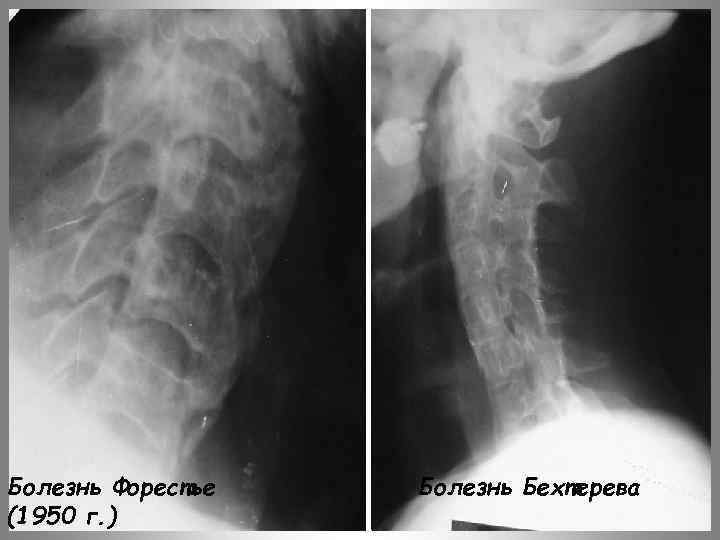

Болезнь Форестье(1950 г. )

Болезнь Форестье (1950 г. ) Болезнь Бехтерева